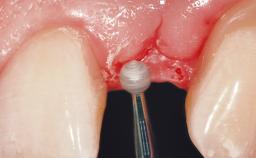

Immediate Flapless Placement of an Implant in a Maxillary Left Central Incisor Site

A 42-year-old female patient was referred to our clinic at the School of Dentistry of the University of São Paulo in November 2004, presenting a deficient restoration in the upper left central incisor. The clinical examination revealed no gingival retraction or any signs of gingival inflammation and, therefore, previous periodontal treatment was not considered. The patient presented a high lip line at full smile and a thin tissue biotype. This combination characterized a high-risk situation from an anatomic point of view, which required careful preoperative planning and cautious surgical execution.

Lip Line No exposure of papillae Exposure of papillae Full exposure of mucosa margin

Periodontal Phenotype Low-scalloped, thick Medium-scalloped, medium-thick High-scalloped, thin

Soft Tissue Contour and Volume Ideal